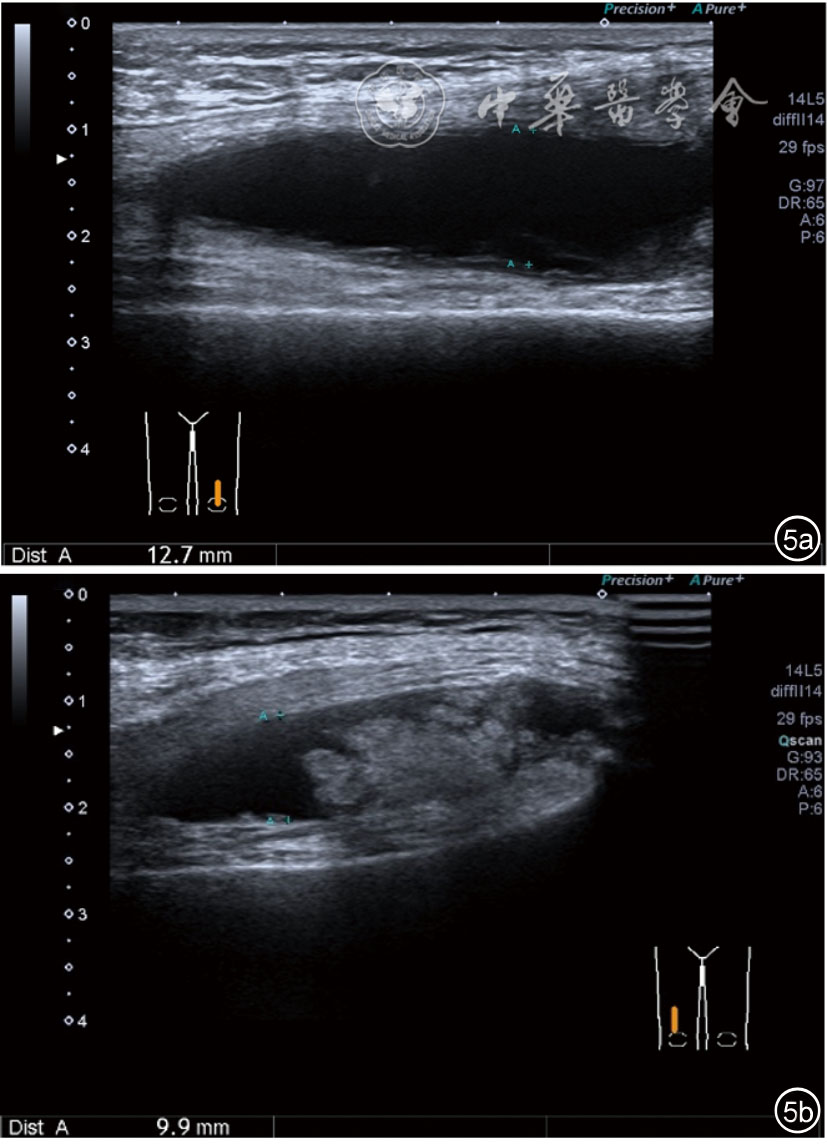

1.关节内表现。(1)骨改变。表现为骨末端或关节周缘出现的骨质局部突起改变,其后方伴或不伴有声影,多见于膝关节内侧缘和外侧缘(图1)。(2)软骨改变。股骨关节面改变可以在长轴及短轴切面显示,嘱患者屈曲膝关节,足平置于检查床,股骨滑车及股骨髁上半部分的关节面即可轻松显示。超声探查可见股骨负重面关节软骨发生不同程度的改变,轻者关节软骨浅侧边界模糊,重者可见关节软骨薄、缺失,软骨下骨缺损改变(图2)。(3)半月板外突。一般内侧半月板突出多见,外侧半月板突出比较少。半月板可见不同程度的外突,同时伴有膝内侧副韧带向外移位(图3)。半月板外周缘性滑脱是指半月板突出超出胫骨平台边缘的距离≥3 mm,其可引起一系列临床症状,早期诊断、早期治疗可以预防骨关节的进一步损伤。(4)交叉韧带损伤。可见前后交叉韧带增粗,回声减低(图4)。(5)髌上囊积液。膝关节是最容易发生积液的关节之一。患者仰卧位,关节积液最常见于膝关节上外侧,因为关节囊向髌股关节上外侧突出。髌上囊积液采用10~18 MHz的高频线阵探头于股四头肌腱纵断面及横断面扫查均可显示,探头频率取决于患者体型。超声可见低回声积液,慢性可伴有丛状滑膜增生(图5)。(6)脂肪垫水肿。脂肪垫在髌骨附着点处回声增强、增厚(图6)。

图5 髌上囊积液、滑膜增生超声图像